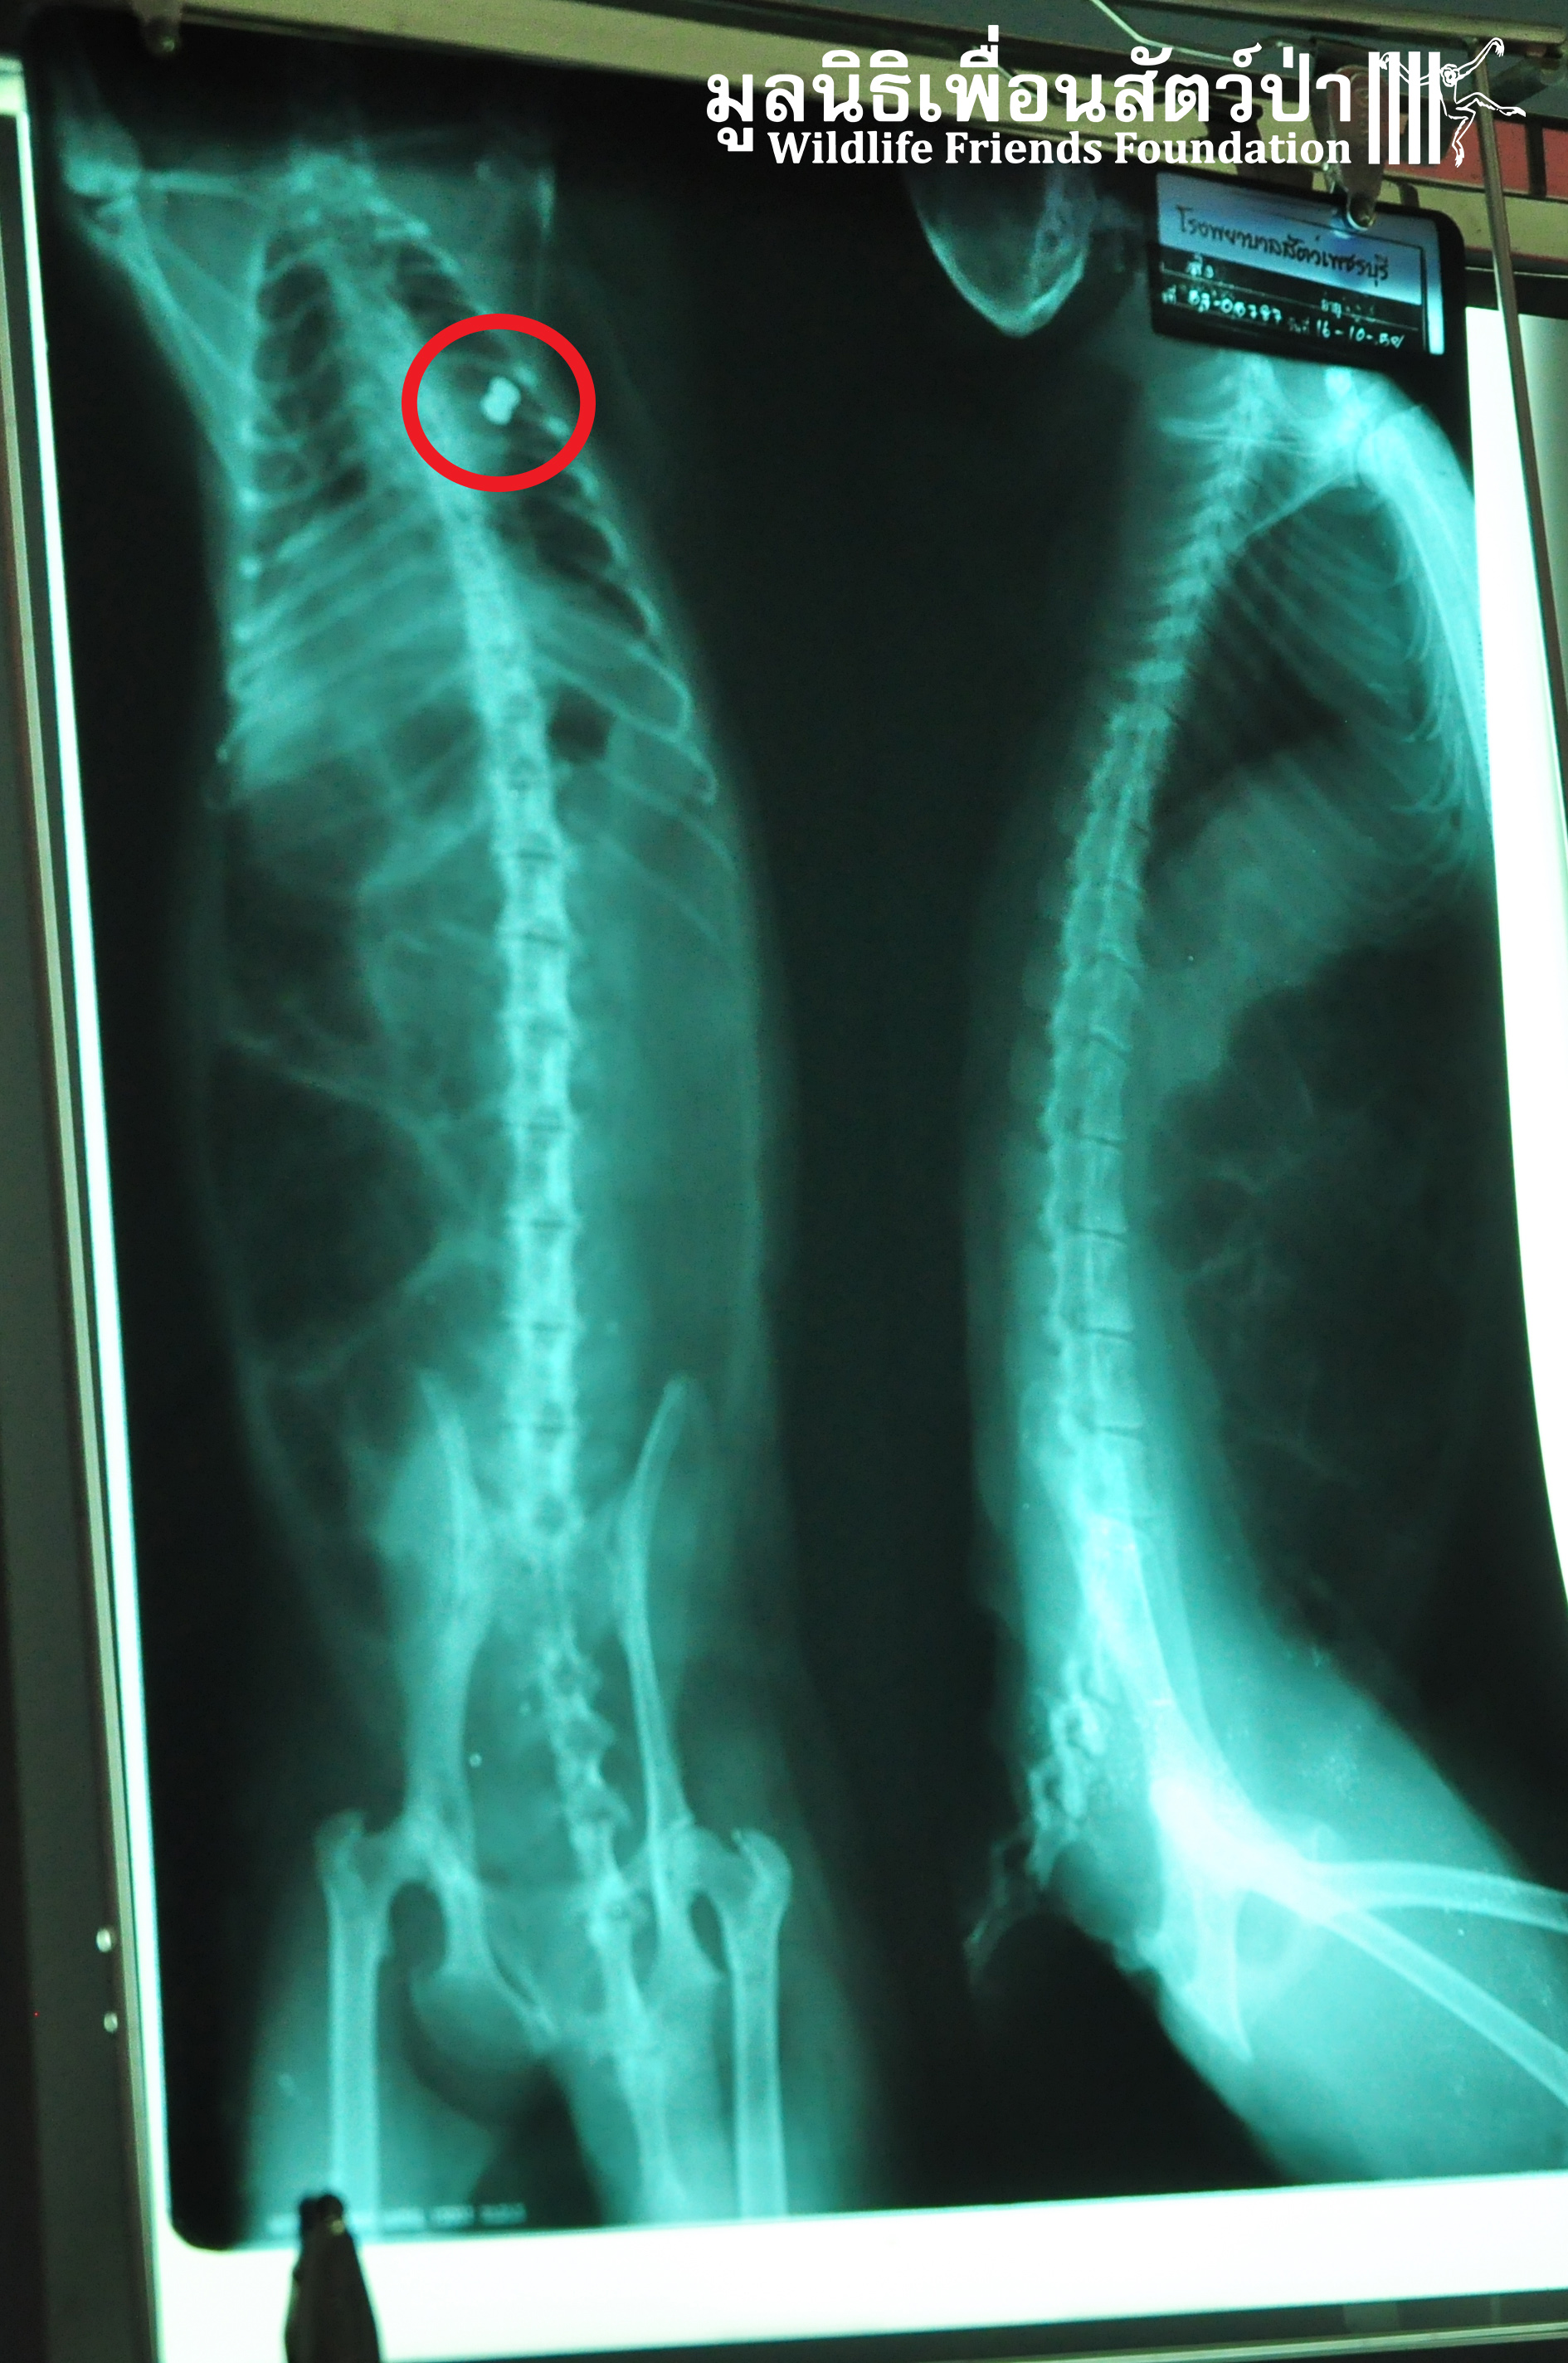

We received a call from the Petchaburi Livestock Department for assistance with an injured long-tailed macaque. A concerned monk had brought the injured macaque to the livestock dept. from Wat Khao Wang in Petchaburi for urgent veterinary treatment. Someone had shot this adult male macaque, the WFFT Rescue Team rushed to the aid of this macaque. Sadly he passed away before reaching the WFFT Wildlife Rescue Centre. We found numerous bullets in his body; it appears that he died from infections due to the bullet wounds. The concerned monks collected the macaque to take him back to the temple, to perform a ceremony and burry him. Human-wildlife conflict is increasing at an alarming rate here in Thailand, particularly with urban macaque populations.